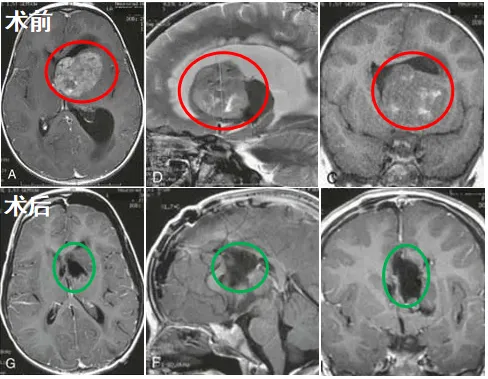

当我在医院见到瑟琳娜时,她仍躺在病床上,意识不清。医生拿着MRI影像向我走来,指着片中明显的巨大侧脑室肿瘤说道:“您女儿情况十分危急。”我下意识追问,医生表示:“脑积水已导致患儿脑组织明显受挤压变形,该肿瘤已严重危及生命,必须立即抢救,否则将错过时机!”

情况紧急,巴教授向我详细说明了手术计划:首先通过脑室外引流术缓解危及生命的脑积水,随后在精密神经导航辅助下,为瑟琳娜实施高难度的肿瘤切除手术。

征得我的同意后,女儿被推入手术室。经过数小时煎熬等待,巴教授走出手术室,微笑着告诉我肿瘤已全切,手术非常成功。我紧绷的情绪终于释放,瞬间泪流满面——我可爱的女儿瑟琳娜得救了。

尽管女儿的肿瘤属于高级别间变性室管膜瘤,后续还需放疗和化疗,但我知道,我们已成功闯过当前最危急的关卡,为后续辅助治疗奠定了重要基础。